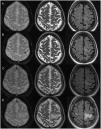

ResultsIn all three cases MRI showed the cortical hypointensity adjacent to the white-matter lesion in the T2-weighted gradient-echo sequence. In the patient with multiple sclerosis, this sign appeared earlier than the abnormal signal in the white matter. The patient being treated with rituximab was diagnosed postmortem and the pathology findings correlated with the MRI findings.

ResultadosEn los tres casos se observa en la RM el hallazgo de hipointensidad cortical adyacente a la lesión de la sustancia blanca en la secuencia EGT2. En la paciente con esclerosis múltiple, este signo fue más precoz que la alteración de señal en la sustancia blanca. El paciente en tratamiento con rituximab fue diagnosticado post mortem y se presenta una correlación radiopatológica.